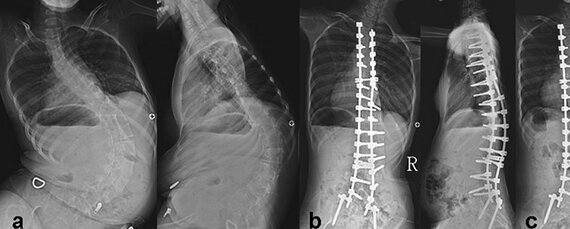

Без необходимого тонуса мышцы постепенно атрофируются. Отсутствие мышц пресса и спины приводит, кроме прочего, к обширным искривлениям позвоночника, а они – к проблемам с дыханием, которые из-за слабых мышц и так есть.

СМА II, болезнь Дубовица. Первые проявления болезни в 7-18 месяцев. Человек с таким типом СМА может есть и сидеть, но не ходит самостоятельно. Продолжительность жизни зависит от степени поражения мышц, обеспечивающих дыхание.

СМА III, болезнь Кюгельберга-Веландер. Болезнь впервые проявляется после полутора лет. Такие больные могут стоять (испытывая боль), но не ходят. На продолжительность жизни СМА III типа, как правило, не влияет, но сильно ухудшает её качество.

Симптомы – мышечная слабость, сколиоз и тремор. Кроме того, развиваются контрактуры суставов (ограничения подвижности в суставах) и нарушения метаболизма.

Менее тяжёлым больным нужны лекарства, облегчающие дыхание, корсеты,  коляски и другие приспособления, облегчающие перемещение и жизнь людей со слабыми мышцами.